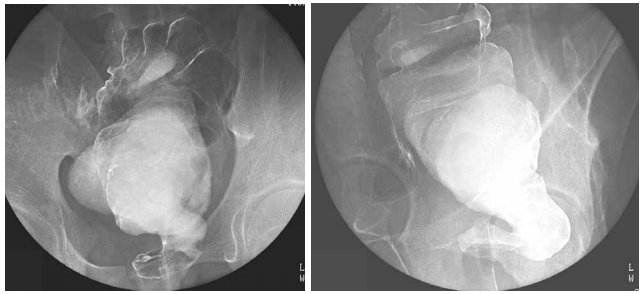

21 一位剛出生的男嬰,身體檢查發現下腹部有一個大膀胱,而且腹部前方可以觸摸得到雙側腎臟。嬰 兒室護士觀察到男嬰的尿液會由尿道口一滴一滴滲出到尿布上。膀胱尿道攝影檢查(voiding cystourethrogram)如附圖所示。下列何者為最可能之診斷?

(A)腎盂輸尿管交接處阻塞(ureteropelvic junction obstruction) (B)輸尿管膀胱交接處阻塞(ureterovesicle junction obstruction) (C)後尿道瓣(posterior urethral valves) (D) Prune-belly 症候群(Prune-belly syndrome)